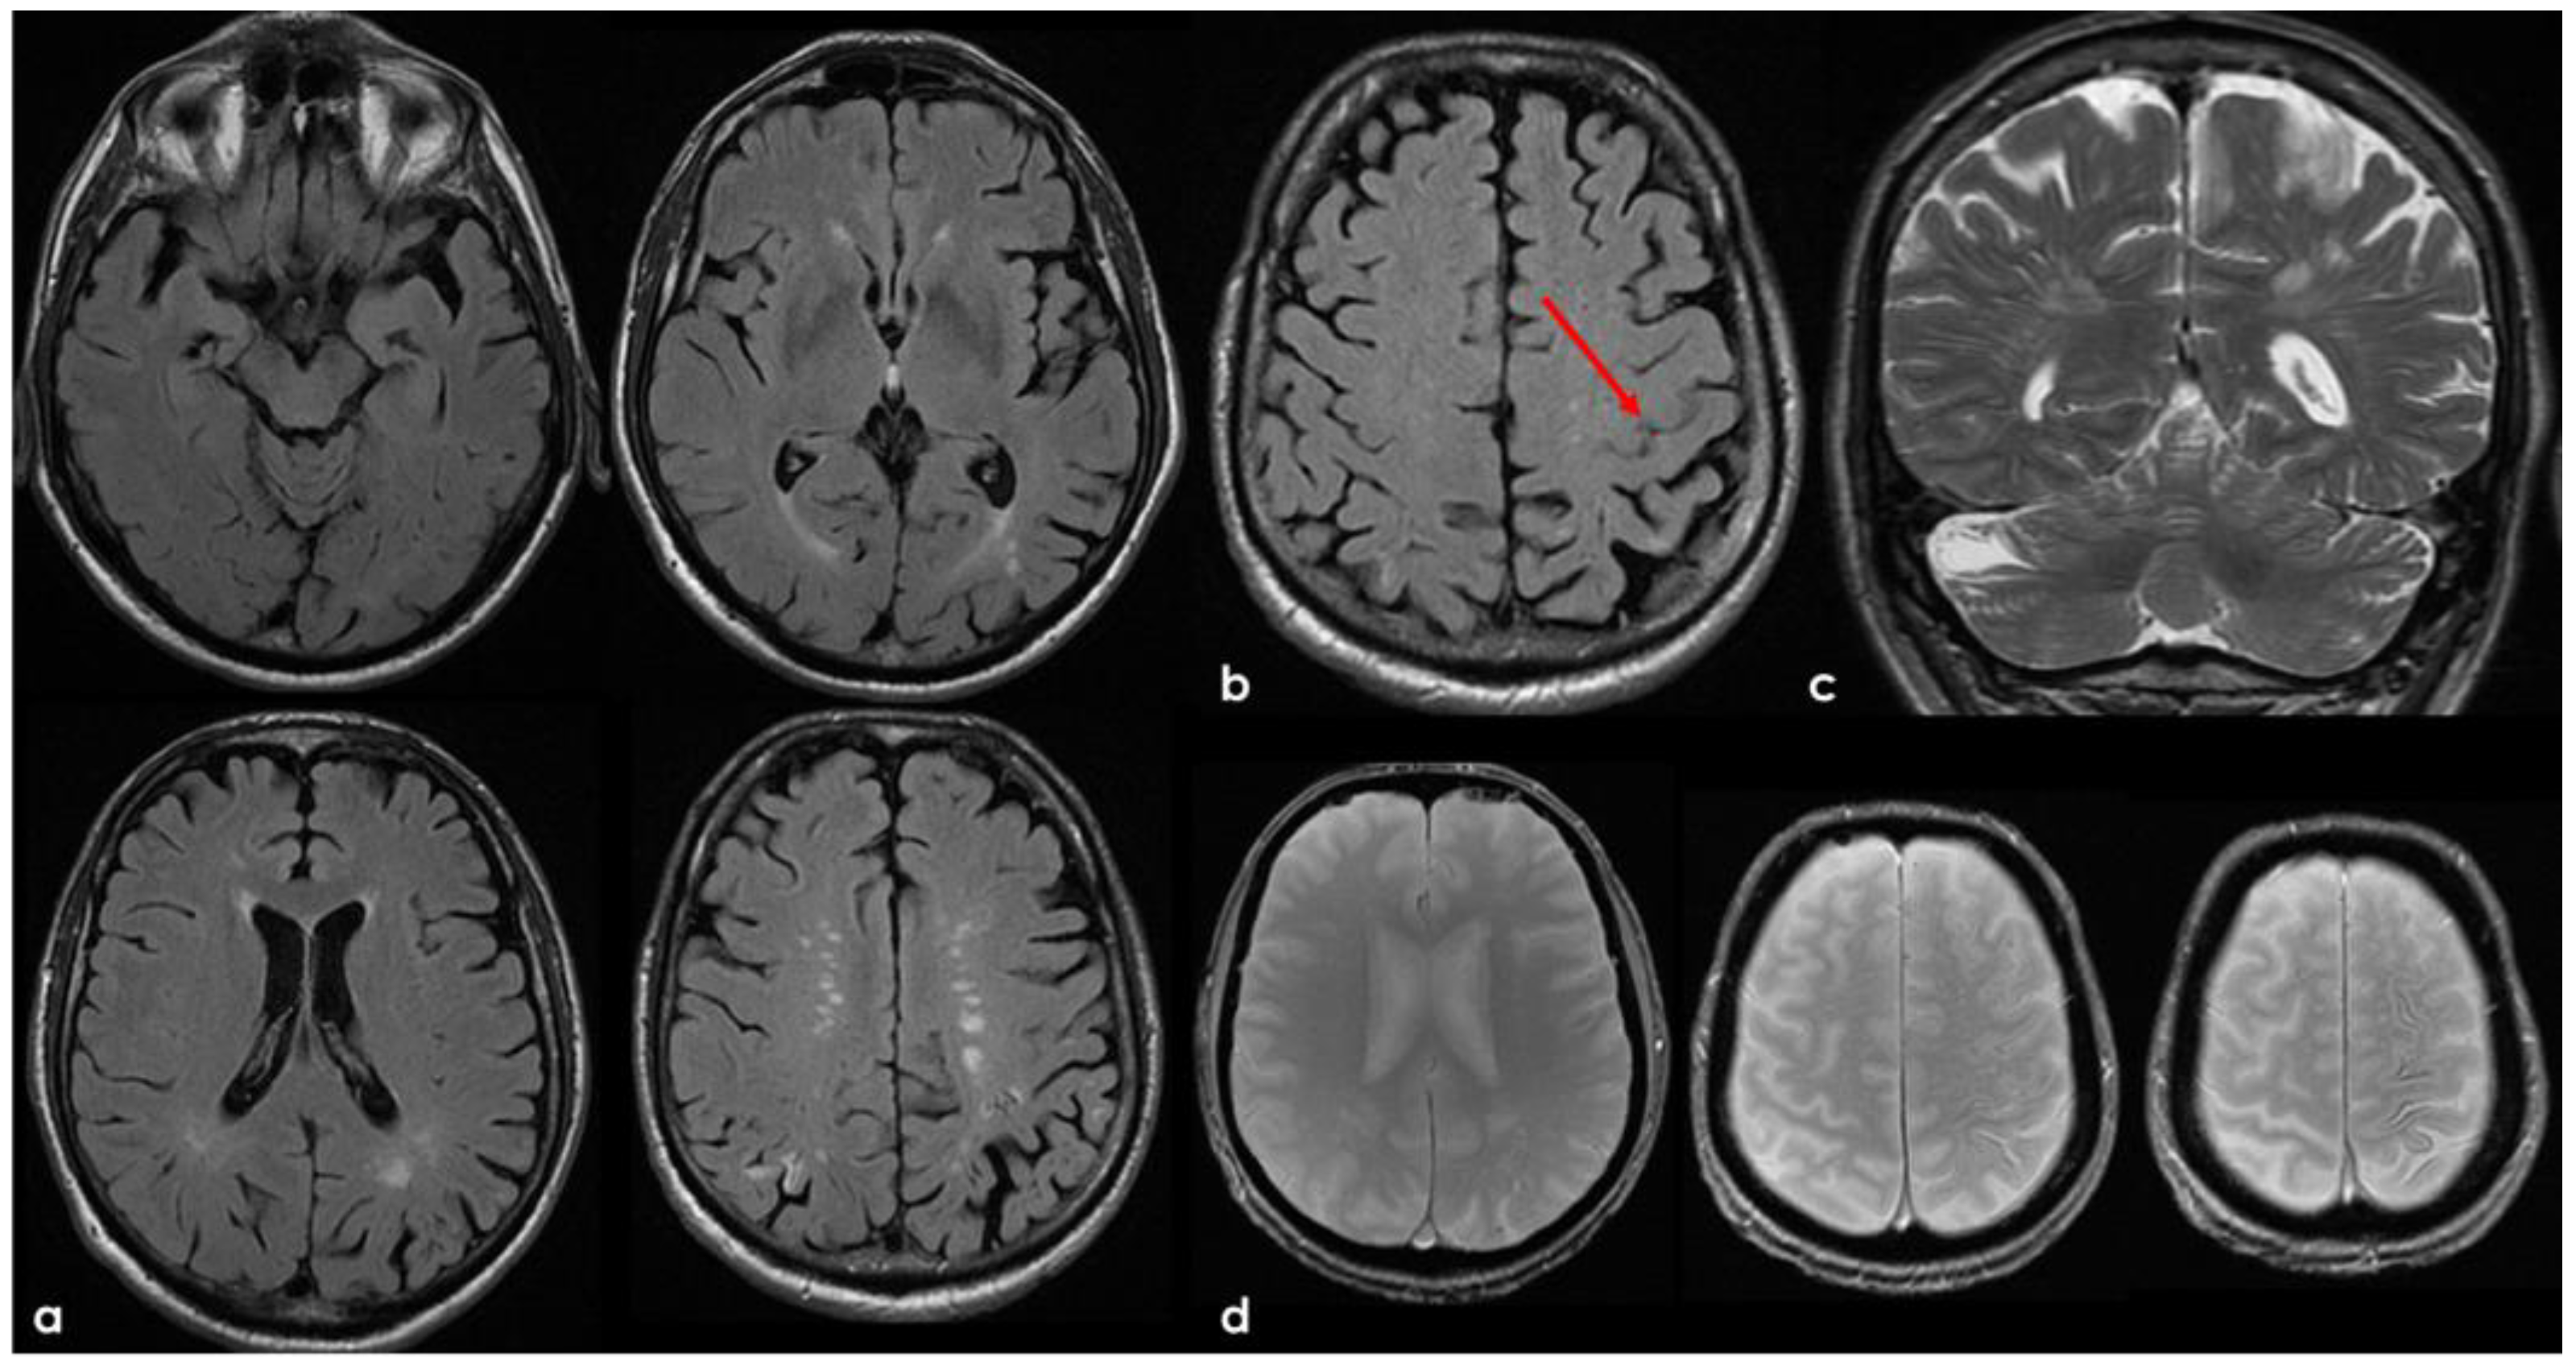

3. May 2014: CAA-Related Inflammation

4. December 2015: Ischemic Stroke